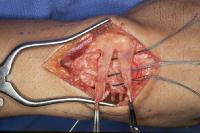

Complete scapholunate ligament disruption seen intraoperatively. A strip of extensor retinaculum is harvested as a ligament graft, left attached to the triquetrum. (Right hand, fingers to the right)

Click for larger image

Intraoperative correction of scapholunate rotation using K-wires as joysticks on each bone.